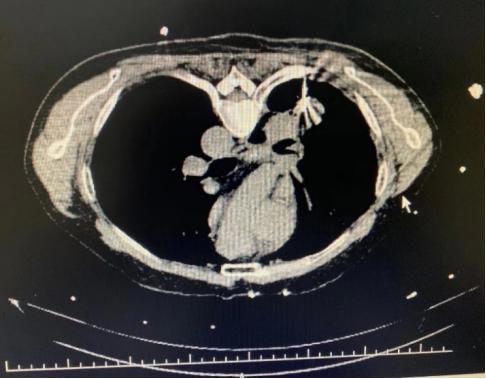

CT引导下肺肿物穿刺活检

CT引导下肺肿物消融治疗